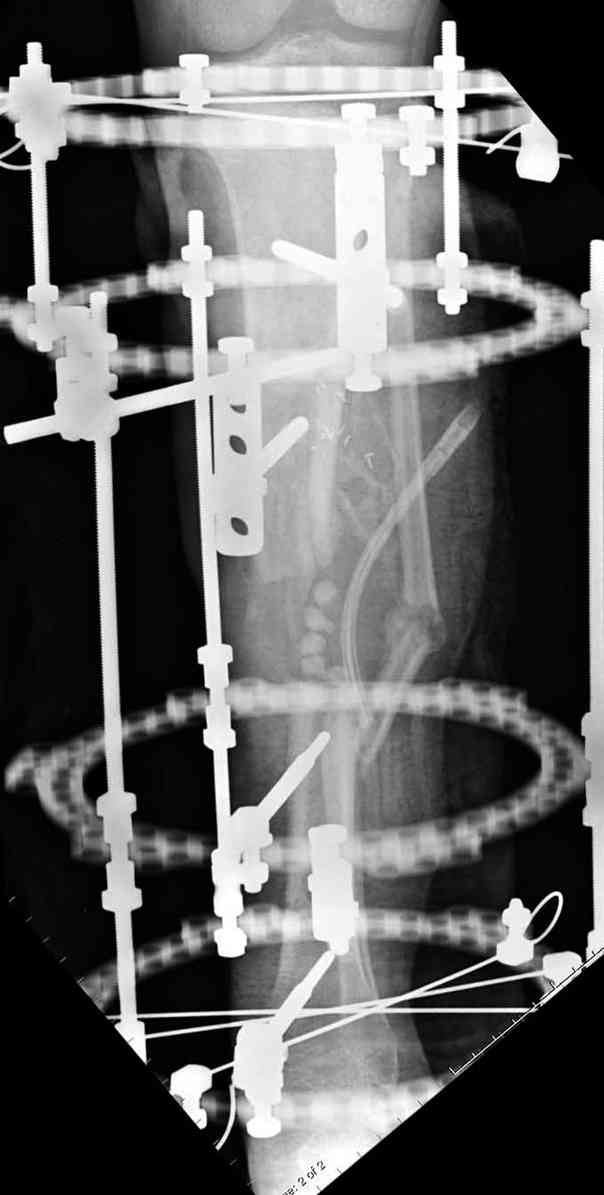

сделать поперечную остеотомию диафиза, полость заполнить antibiotic beads и начать удлинение.

Из аппаратов предпочтительно циркулярный, на дистальном фрагменте можно увеличить количество спиц.

Здесь случай, хотя не тот уровень, но принцип "удлинения после заполнения дефекта Antibiotic Beads" сохранен, можно немного увеличить количество бус.